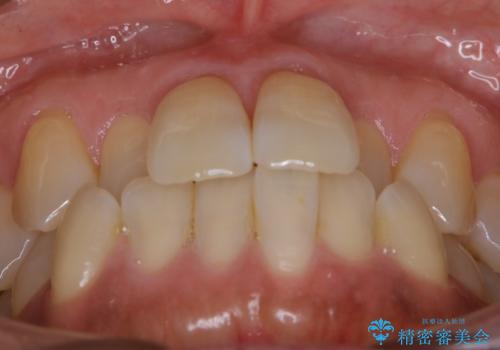

【非抜歯】短期間で実現する前歯の反対咬合治療

- 前歯のガタつきを主訴に来院されました。

奥歯の噛み合わせにはほとんど問題が見られず、歯列拡大とIPRのみの必要最低限の移動で歯並びの治療を計画することとなりました。